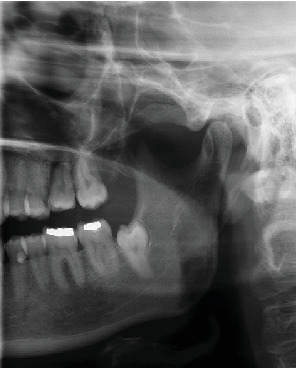

自体牙移植的效果主要取决于移植牙的解剖结构、供牙的类型和牙根形成的发育阶段。成熟牙由于牙髓血运重建潜力较低,并发症发生率较高,需要术前或术后进行根管治疗(RCT)以避免术后并发症,延长了治疗时间和费用。本文报告了一位39岁的患者在根管再治疗失败后,自体移植一颗成熟的智齿来代替第一磨牙。在手术中,移植的牙齿在放置之前进行了口外根切除,以避免需要提升施耐德膜,在手术切除上颌窦囊性病变后,施耐德膜显示不完全愈合。术前和术后均未进行随机对照试验。在3年的随访中,牙齿无症状。使用标准的活力测试难以确定自体移植牙的活力,这取决于患者的主观反应,但使用脉搏血氧仪客观地证实了这一点。本病例不仅显示了老年患者成熟牙移植血运重建的可能性,也为如何客观地确认和测量自移植牙的血运重建提供了可能的术后方案。

The outcome of tooth autotransplantation depends mainly on the transplant tooth's anatomy-the type of donor tooth and the developmental stage of root formation. Mature teeth display a higher complication rate due to lower pulp revascularization potential, requiring root canal treatment (RCT) pre- or postoperatively to avoid postoperative complications, which extends treatment duration and cost. This report details a 39-year-old patient's autotransplantation of a mature wisdom tooth to replace the first molar after unsuccessful root canal retreatment. During the surgery, an extraoral root resection of the transplanted tooth was performed prior to placement to avoid the need to elevate the Schneiderian membrane, which displayed imperfect healing following the surgical removal of a cystic lesion in the maxillary sinus. RCT was not performed before nor after the procedure. At the 3-year follow-up, the tooth was asymptomatic. The vitality of the autotransplanted tooth was difficult to determine using standard vitality tests, which depend on patients' subjective responses, but the use of pulse oximetry objectively confirmed this. This case not only shows the possibility of a mature tooth transplant revascularization in an older patient but also gives a possible postoperative protocol of how to objectively confirm and measure the revascularization of the autotransplanted tooth.